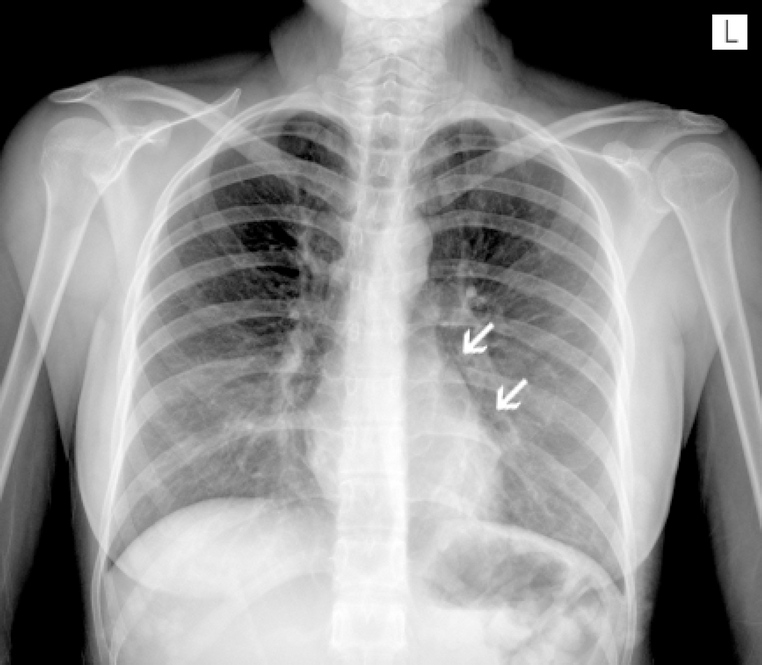

El electrocardiograma mostró evidencia de arritmia sinusal, sin datos de sobrecarga del ventrículo derecho ni cambios del segmento ST. La prueba de PCR en tiempo real, realizada únicamente contra el virus de la influenza A H1N1, fue negativa. En la radiografía de tórax, en proyección posteroanterior, se observó aire libre en el mediastino (Figura 1), así como en la cara lateral izquierda del cuello (Figura 2). Al día siguiente de su hospitalización se agregó dolor torácico, que se incrementaba en la inspiración.

Figura 1 Radiografía de tórax donde se observa imagen radiolúcida en el borde izquierdo del mediastino.